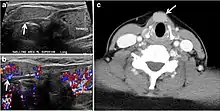

- Fig. 4. A 45-year-old male patient presented with anterior mediastinal metastatic PTC lesions and occult primary on imaging. Histopathology examination of the resected thyroid gland revealed micro-foci of PTC; the largest, in the isthmus, measured 4 mm. a transverse greyscale ultrasound of the thyroid demonstrates homogeneous gland with normal echogenicity and size. No focal lesion or micro-calcifications. b Non-enhanced CT scan obtained as part of PET/CT examination shows a heterogeneous, large, relatively dense anterior mediastinal mass (white arrow) with peripheral calcification (arrowheads). Thyroid gland has normal CT appearance with no abnormal FDG uptake (not shown).[1]

- Fig. 9. A 58-year-old male patient with persistence PTC at thyroid bed with hypervascular nodal metastasis. a–c Transverse greyscale and colour Doppler neck ultrasound demonstrate hypoehoic soft tissue in the left thyroid bed (white arrow in a). There are a heterogeneous enlarged lymph nodes at level 2 and 3 with markedly increased vascularity (white arrow in b and c). d–f Enhanced axial CT images of the neck demonstrate a 2.7 × 1.4 cm hypodense soft tissue lesion anterior to the left carotid sheath (white arrow). There are left-sided enhancing abnormal and enlarged lymph nodes at cervical level 2 and 3 (black arrows).[1]